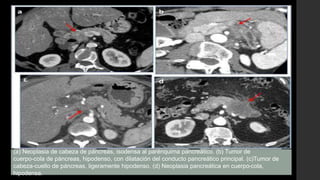

(a) Neoplasia de cabeza de páncreas, isodensa al parénquima pancreático. (b) Tumor de

cuerpo-cola de páncreas, hipodenso, con dilatación del conducto pancreático principal. (c)Tumor de

cabeza-cuello de páncreas, ligeramente hipodenso. (d) Neoplasia pancreática en cuerpo-cola,

hipodensa.

Localización de la lesión: •Cabeza-proceso uncinado(65%) •Cuerpo (20-25%) •Cola (10-20%) Tamaño del tumor: •Permite estadificar y valorar la respuesta tras el tratamiento en el seguimiento Densidad tras la administración de contraste iv: • Hipodensa: la mayoría de los tumores. • Isodensa (10%): es más frecuente que los tumores sean isodensos al resto del parénquima pancreático cuando su tamaño ≤2 cm. (a) Neoplasia de cabeza de páncreas, isodensa al parénquima pancreático. (b) Tumor de cuerpo-cola de páncreas, hipodenso, con dilatación del conducto pancreático principal. (c)Tumor de cabeza-cuello de páncreas, ligeramente hipodenso. (d) Neoplasia pancreática en cuerpo-cola, hipodensa.